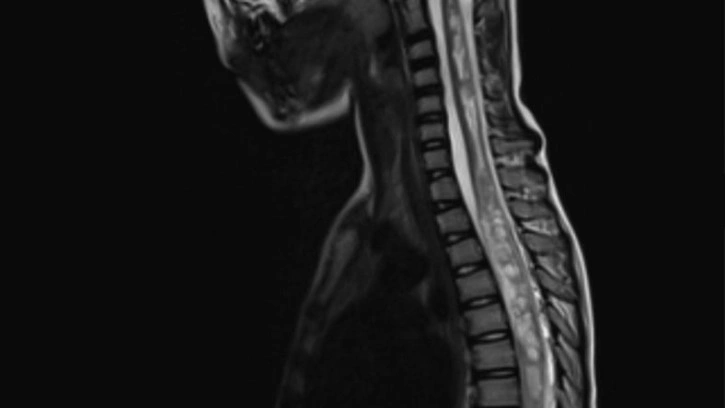

Kaliforniya Üniversitesi bünyesinde çalışmalarını sürdüren bir grup bilim insanı, "fonksiyonel ultrason görüntüleme" (fUSI) ismini verdikleri yeni bir cerrahi görüntüleme tekniği geliştirdiler. Bu teknik; cerrahlara, omuriliği gerçek zamanlı ve yüksek çözünürlüklü görüntüleme imkânı sağlıyor. Bilim insanları, özellikle de kronik sırt ağrısı çeken insanların, bu yöntem sayesinde iyileşebileceklerini düşünüyorlar.

Geleneksel görüntüleme yöntemleri, omurilikte meydana gelen 2 santimetrelik kan akışı değişikliğini tespit ederler. fUSI isimli yeni teknoloji ise bu seviyeyi 1 milimetrenin altına düşürüyor. Bu çok önemli çünkü uzmanlar, bu sayede uyguladıkları tedavinin omurilik üzerindeki etkisini anında ölçebilecekler. Böylelikle tedavi yönteminin ve hatta bir operasyonun işe yarayıp yaramadığı da anında anlaşılabilecek.

Projeyi sürdüren isimlerden biri olan Vasileios Christopoulos, bu yeni teknolojinin 6 hasta üzerinde denendiğini ve işe yaradığını açıkladı. Bilim insanı, bu hastaların çok uzun zaman boyunca sırt ağrısı ile mücadele ettiklerini, artık son çare olarak ameliyat edildiklerini söyledi. İşte ameliyat sırasında fUSI'den yardım alındı. Omurilik, anlık olarak görüntülendi ve ameliyatın etkili olup olmadığı takip edildi.